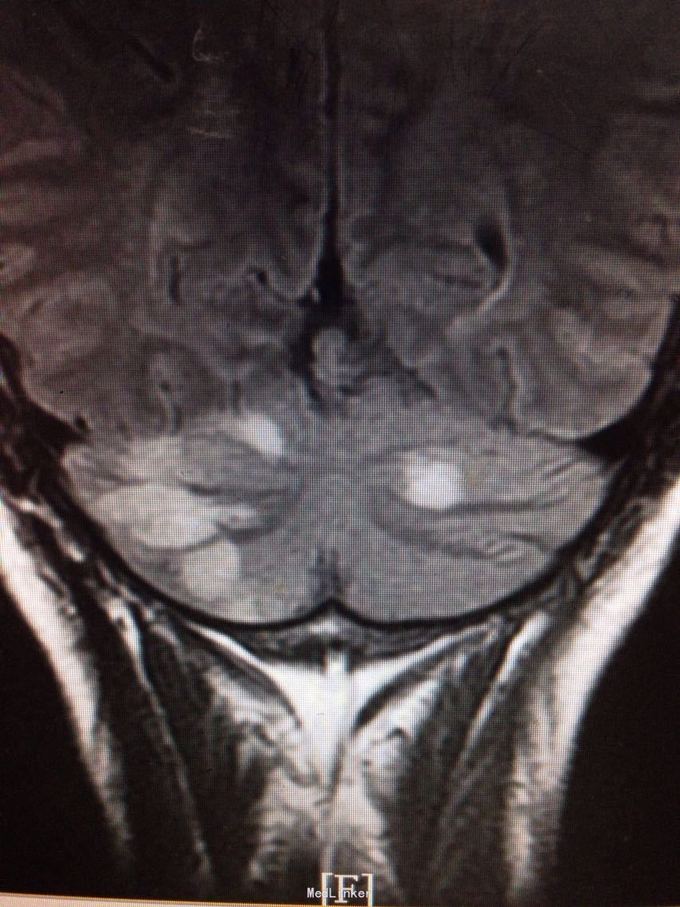

患者为59岁男性,因头晕、头痛、行走不稳7天入院。患者缘于7天前无明显诱因感头晕,伴视物旋转、视物模糊、恶心,静坐约20分钟可缓解,伴头痛,右侧肢体乏力,行走不稳,症状反复。遂来我院。既往有高血压病史。

查体:双侧瞳孔等大等圆,直径2mm,双眼左视可见震颤,Romberg征阴性,跟膝胫试验欠稳准,NIHSS评分3分,洼田饮水试验1级。 我院急诊头颅CT示:双侧小脑半球片状低密度影,考虑脑梗塞。 颅脑MRI示:双侧小脑半球多发急性脑梗塞,以右侧为著。

诊断为脑梗死(急性期,双侧小脑半球) 治疗上予双抗血小板,改善循环,营养神经,清除自由基及降脂稳定斑块等治疗。